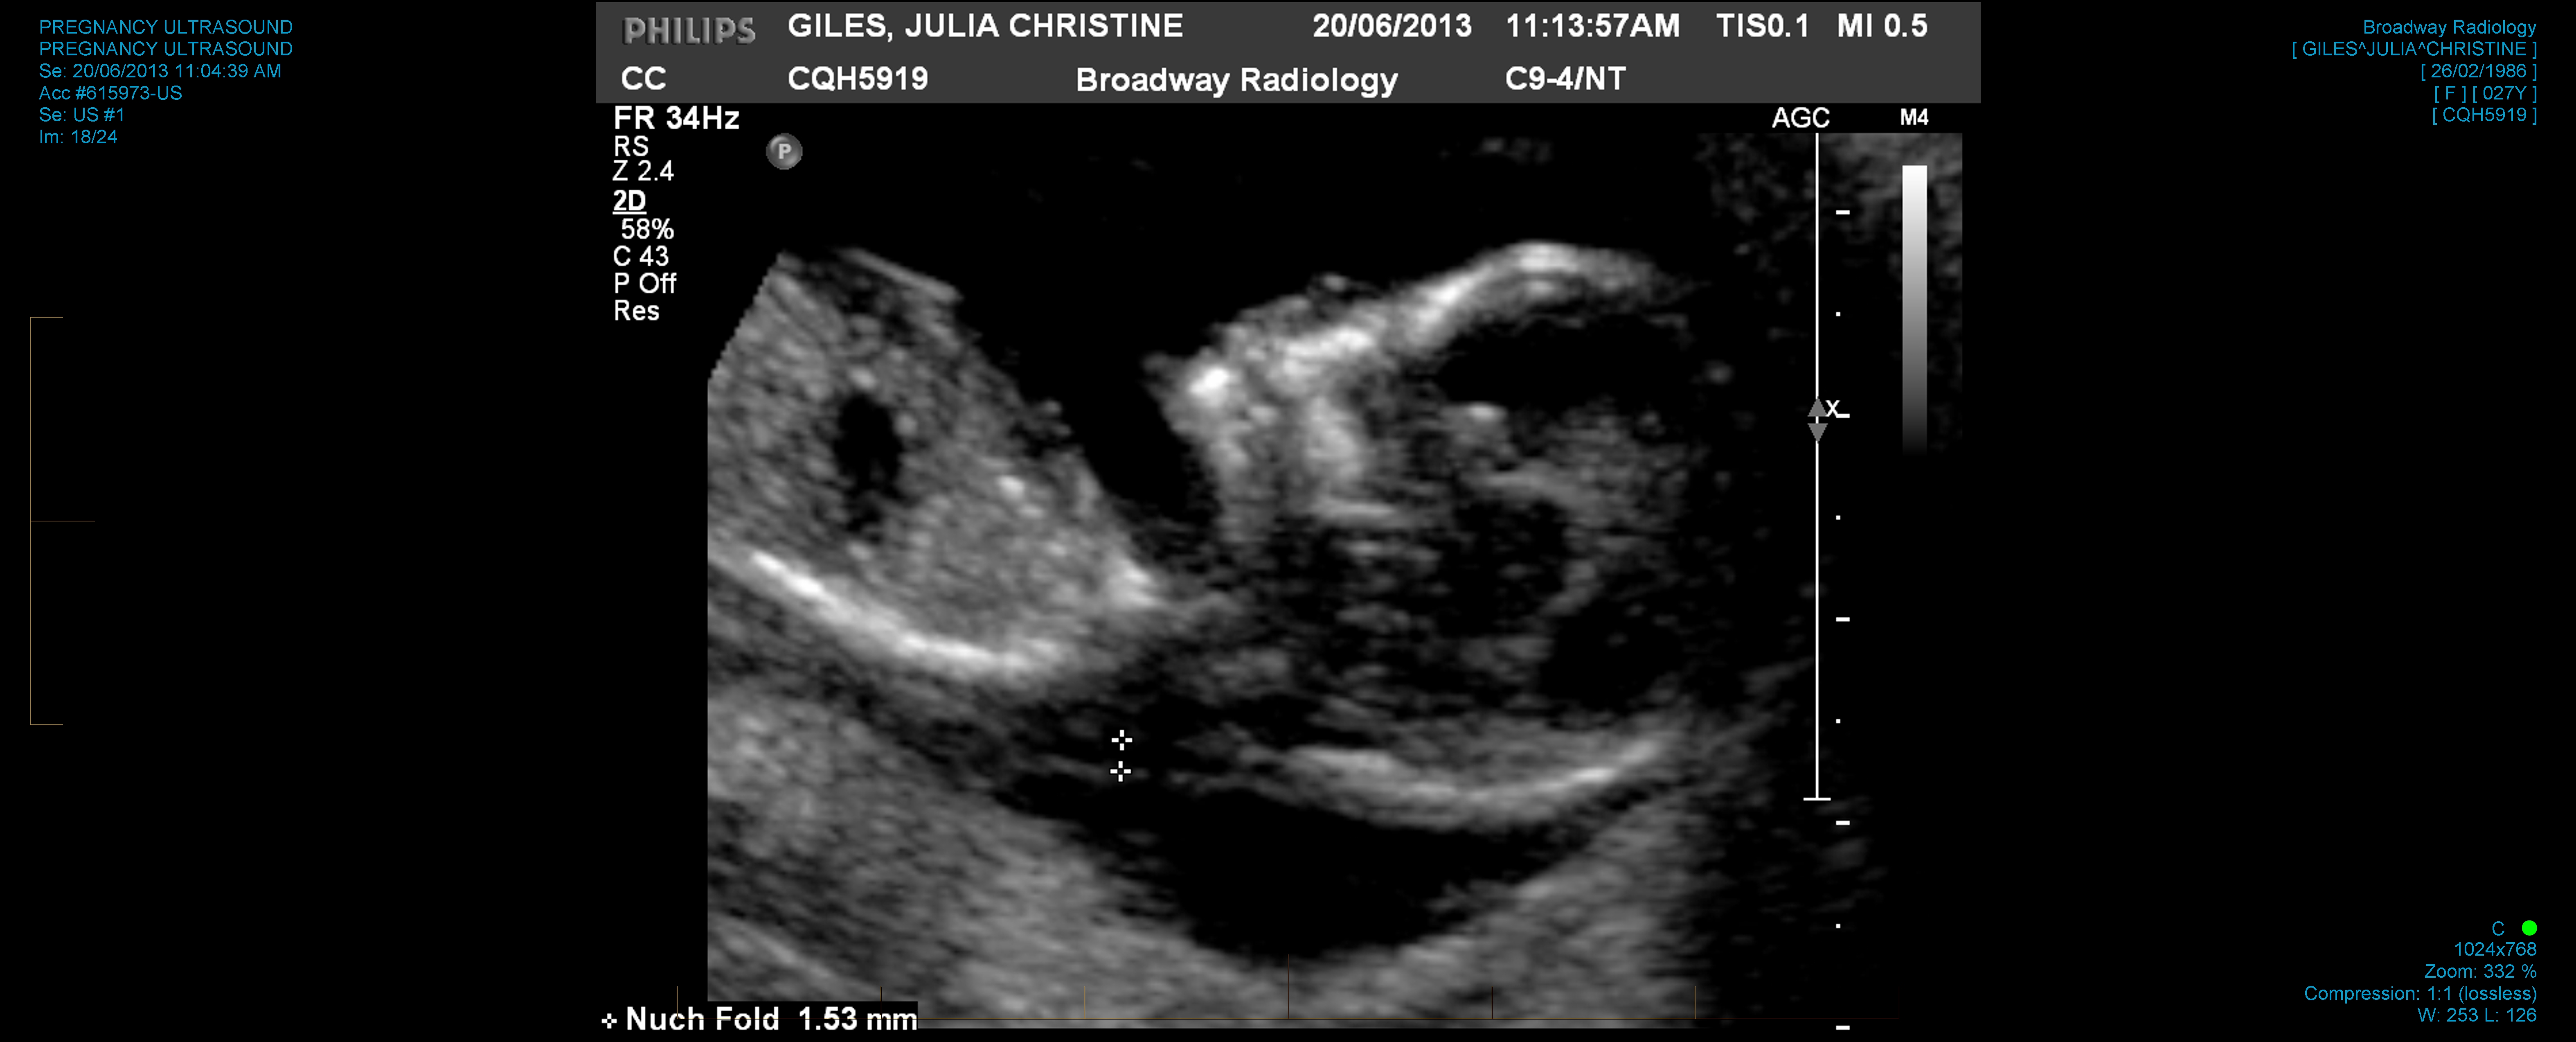

Here's photographic proof (click for bigger pictures, if for some reason you are interested in ultrasound photos of my future child):